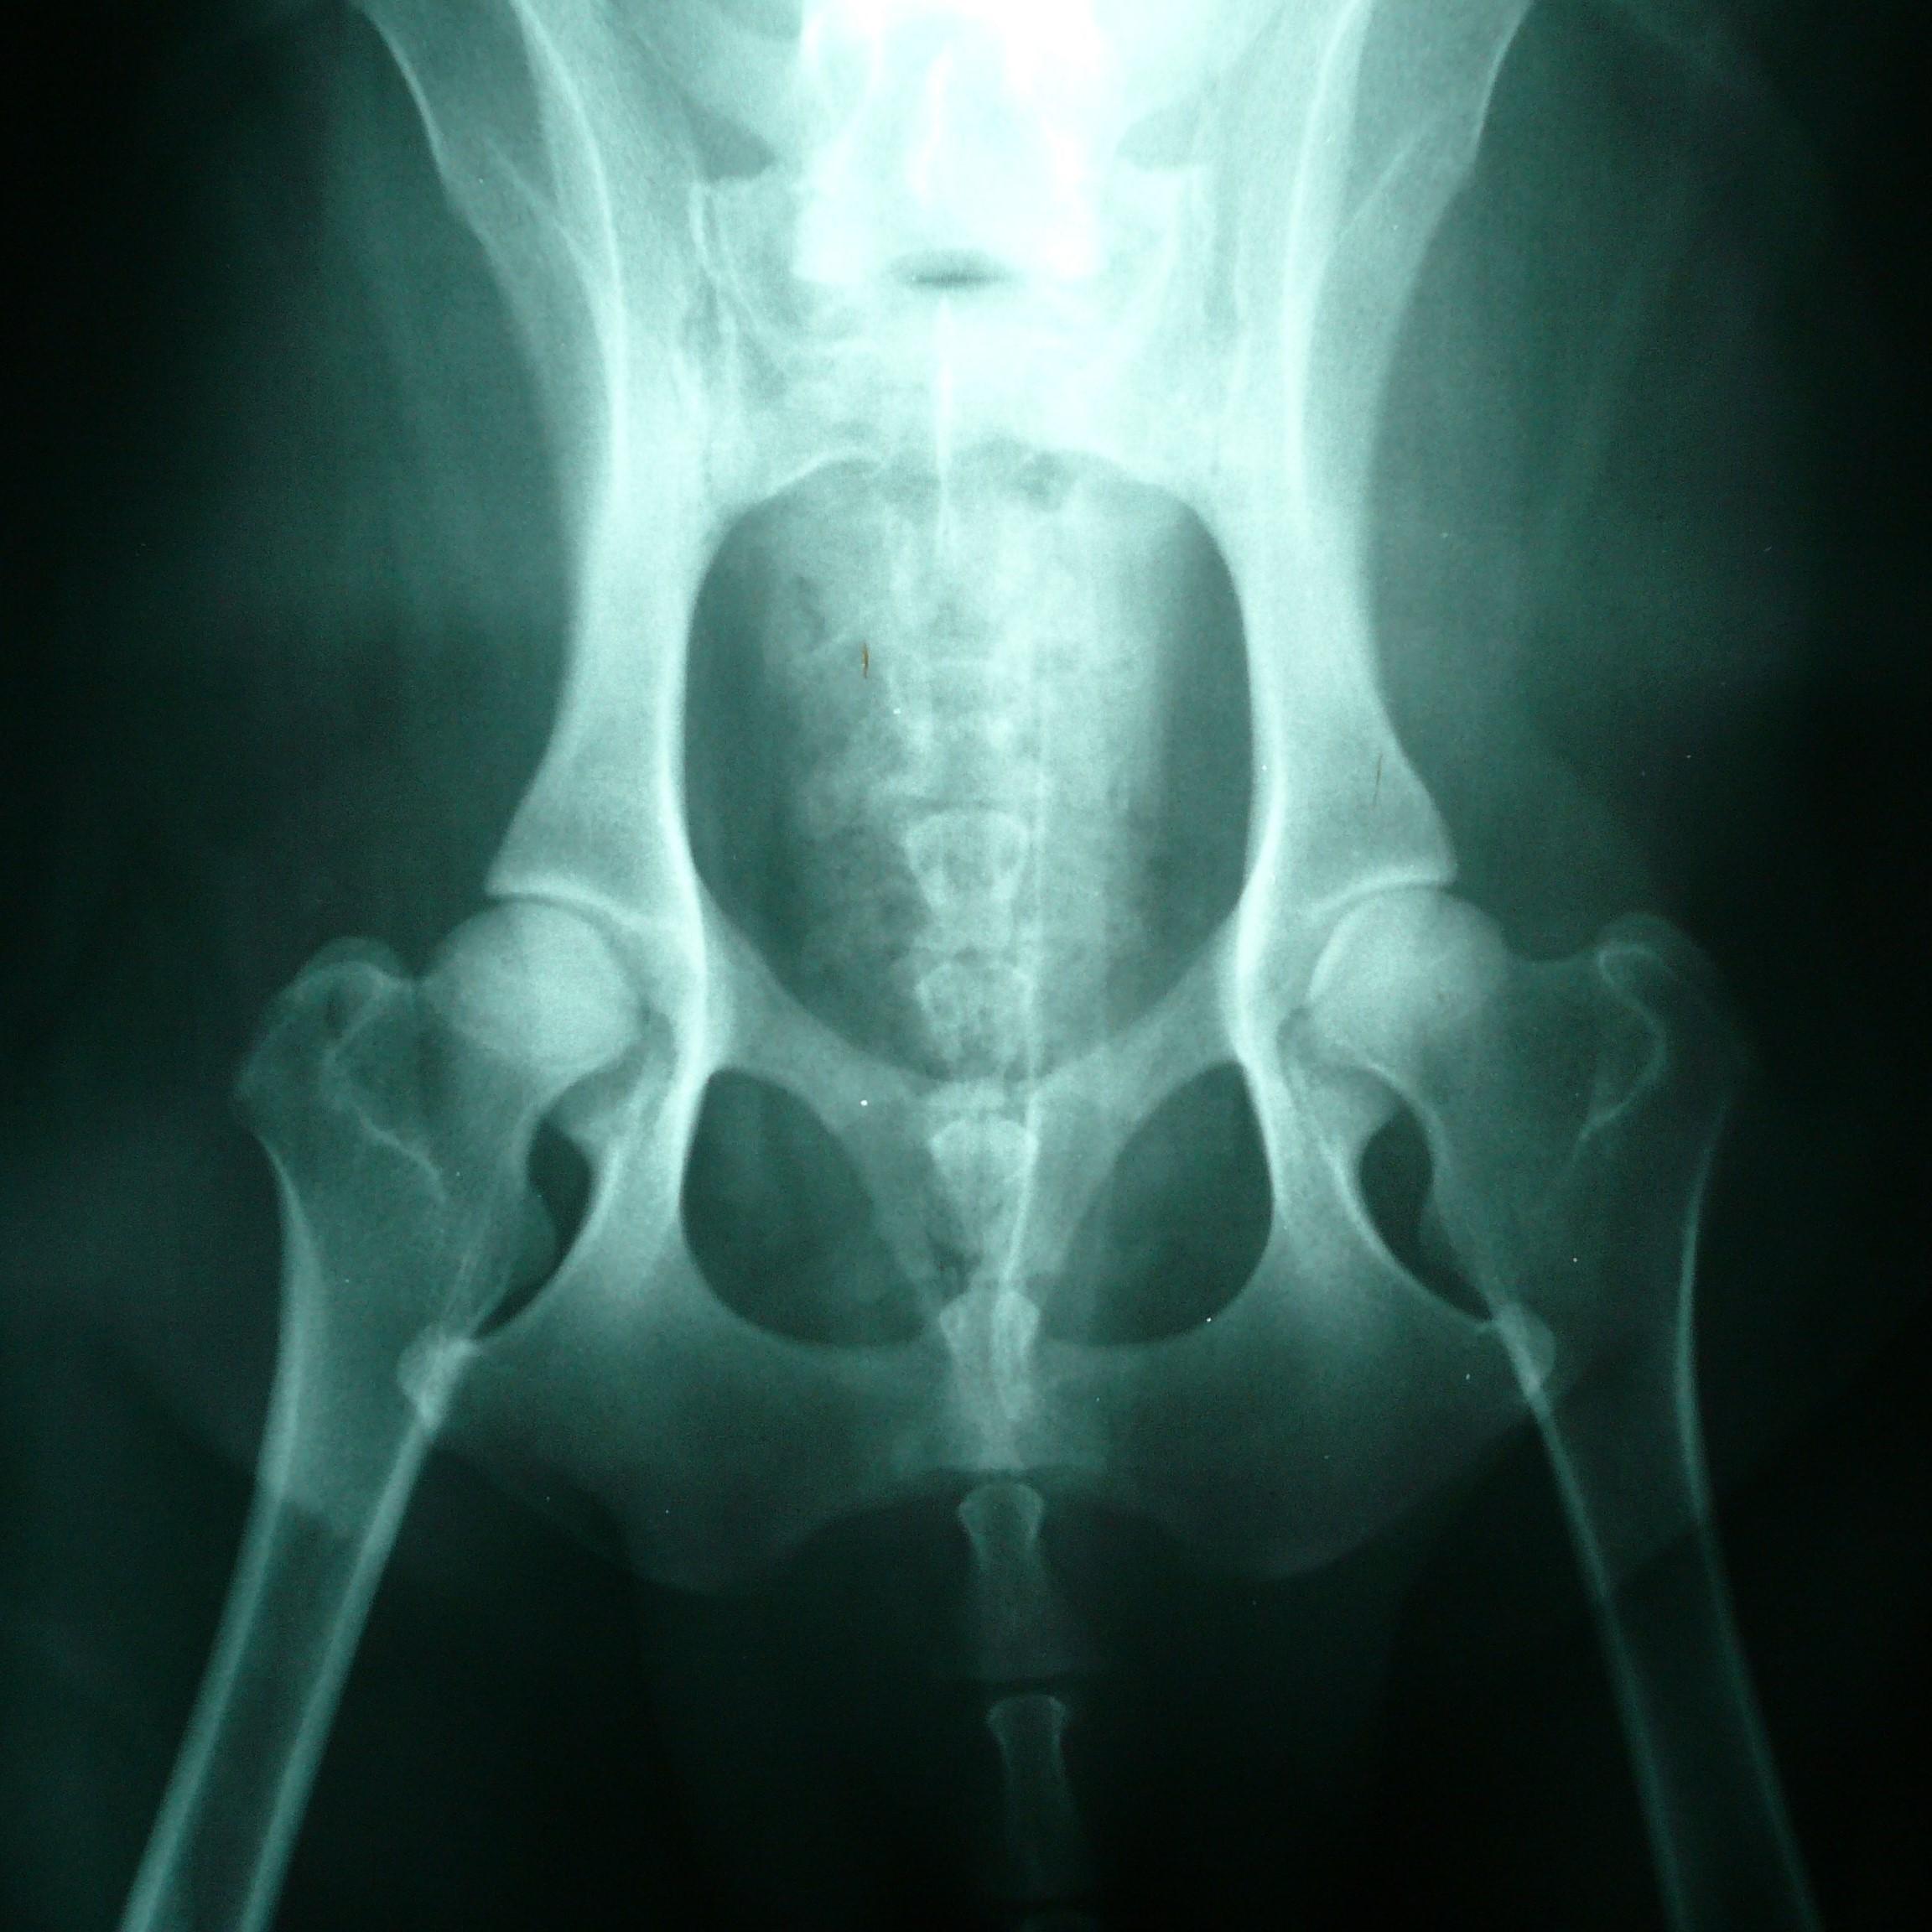

La displasia de cadera en el golden retriever

La displasia de cadera es una enfermedad hereditaria en la que la articulación de la cadera (articulación coxofemoral) está mal formada y presenta tendencia a dislocarse. Esta patología afecta con frecuencia a razas de perros medianos y grandes, incluyendo al golden retriever.

Se considera una enfermedad genética multifactorial, por lo que el ambiente también juega un papel importante en la manifestación de la displasia de cadera. De esta forma, el ejercicio intenso y la sobrealimentación pueden desarrollar la enfermedad con mayor rapidez, en especial si dichos causantes se producen durante la infancia o adolescencia del can. Una vez evolucionada, si el perro afectado cuenta con los cuidados adecuados puede tener una vida cómoda, tranquila y duradera.

La displasia de cadera no es evidente en cachorros, ya que es una enfermedad que se desarrolla con el paso de la edad. También puede pasar desapercibida en aquellos golden retriever adultos que son resistentes al dolor y, por tanto, no cojean ni muestran otros síntomas evidentes. Sin embargo, a medida que la enfermedad avanza, el perro presenta cojera sin causa aparente.

Es importante descartar a tiempo la presencia de displasia de cadera en el golden retriever a través de una radiografía de la cadera del perro a partir de su primer año de vida. Las placas radiográficas hechas antes de esa edad pueden presentar falsos negativos y, por ende, no son recomendables. Algunos veterinarios recomiendan hacer la radiografía cuando el perro haya alcanzado los dos años de edad para obtener resultados más confiables.

Aunque no todas las sociedades caninas o clubes de golden retriever exigen la placa de caderas, siempre es recomendable hacérsela para descartar o confirmar la presencia de esta enfermedad. Tanto si tienes pensado presentar a tu can a un concurso como si no, su salud siempre es lo más importante.